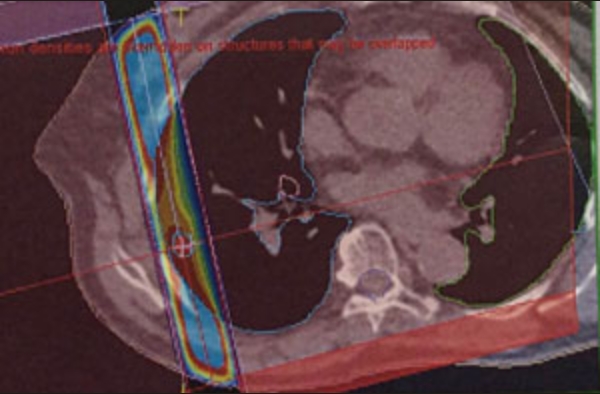

小肺がんの照射

肺がん+リンパ節

はじめのうちは、広く照射。その後、縮小照射正常肺にできるだけ当たらないように3個に分けて照射